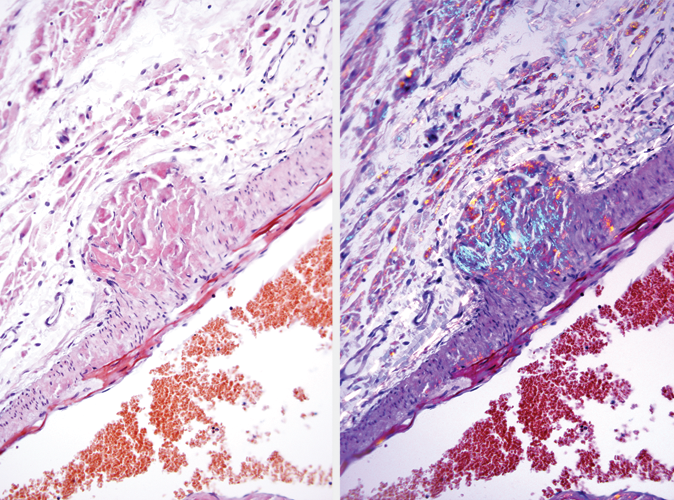

Human leiomyosarcoma: immunohistochemical staining for Muscle Specific Actin. Muscle Specific Actin: clone HHF35

Muscle specific actin (MSA) is a highly conserved, ubiquitous protein found in muscle and some non-muscle cells. Actins can be divided into three subsets, alpha actins found in muscle tissue cells, beta and gamma actins found in non-muscle cells and a small subset of gamma actins also found in muscle tissue cells. In normal tissues, expression is found in striated fibers of skeletal muscle, smooth muscle in arteries, veins and pericytes of smaller arteries, muscle in bowel, myometrium of the uterus, prostatic stroma, capsule cells of liver, kidney, lymph node and spleen, the myoepithelial layers of mammary ducts and glands, eccrine sweat glands and salivary glands. Expression is not found in epithelial cells, lymphoid cells, macrophages, connective tissue and neuronal cells. In neoplastic tissues, expression can be found in soft tissue tumors with muscle differentiation, for example, leiomyomas, leiomyosarcomas and rhabdomyosarcomas of varying subtypes. Non-muscle sarcomas, carcinomas, melanomas and lymphomas do not express muscle specific actin.

Muscle Specific Actin is recommended for the detection of specific antigens of interest in normal and neoplastic tissues, as an adjunct to conventional histopathology using non-immunologic histochemical stains.